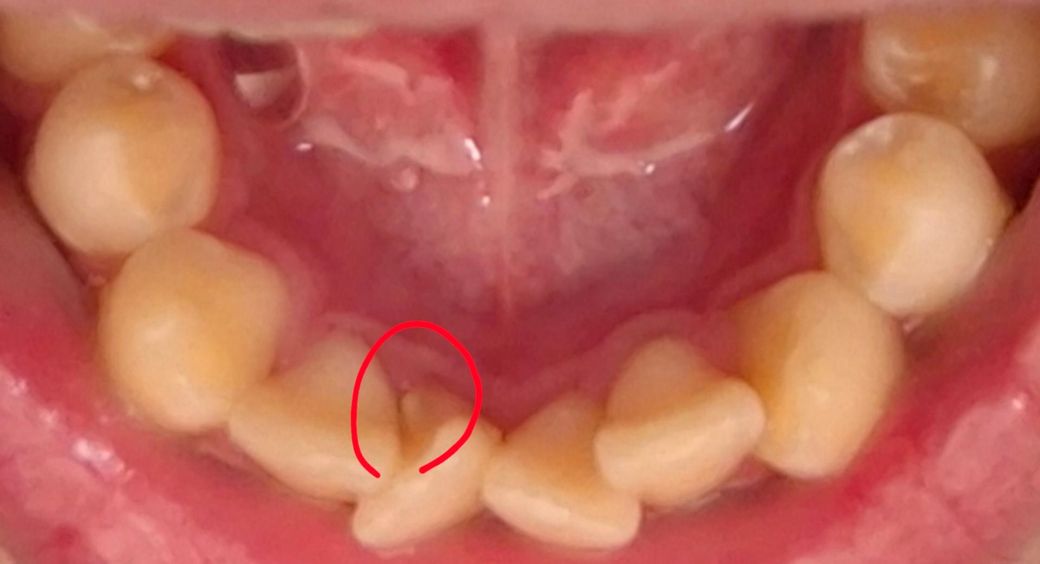

잇몸 뒷편에 있는 딱딱한 무언가가 도대체 무엇일까요?

이게 뭘까요? 만져봤는데 이빨 처럼 딱딱한데 이게 뭘가요? 그냥 이빨일까요? 계속 이것 때문에 불편한데 없에는 방법이있을까요?

얼핏봤을 땐 치아같긴한데 자세히 잘 안보여요. 만약 원래는 없다가 생긴거면 치아는 아니겠구요. 치아처럼 단단하다면 치석일 수도 있는데 다른 부위가 깨끗한 편이신걸로 봐서 그 부분에만 치석이 쌓였을 것 같지는 않네요. 일단 치과에 가셔서 검사받아보세요.

치아의 일부 형태로 보여지며 치아라면 없애는것보다는 적응하고 지내는것이 유리할수 있습니다. 주변부위의 치석으로 인해 이물감이 크게 느껴질수 있으니 스케링 권유드립니다. 건강하세요.

사진으로 보이는 부분은 치아에 튀어나온 부분으로 보입니다. 몇몇 치아들은 사진과 같이 특정 부위가 올라와 있는 경우가 있습니다. 이렇게 올라와 있는 부위에는 신경도 같이 올라가 있는 경우가 있기 때문에 해당 부위가 파절이 되면서 통증을 유발하는 경우도 있습니다. 정확한 확인을 위해서 치과에서 진료를 받아보는 것을 권유드립니다.

사진상 보기에는 치석같습니다. 원래 아래 앞 치아 뒷면에는 치석이 잘 끼고요, 더군다나 치열이 고르지 않으니 더더욱 치석이 잘 낍니다. 치과가서 스케일링 받아보세요.